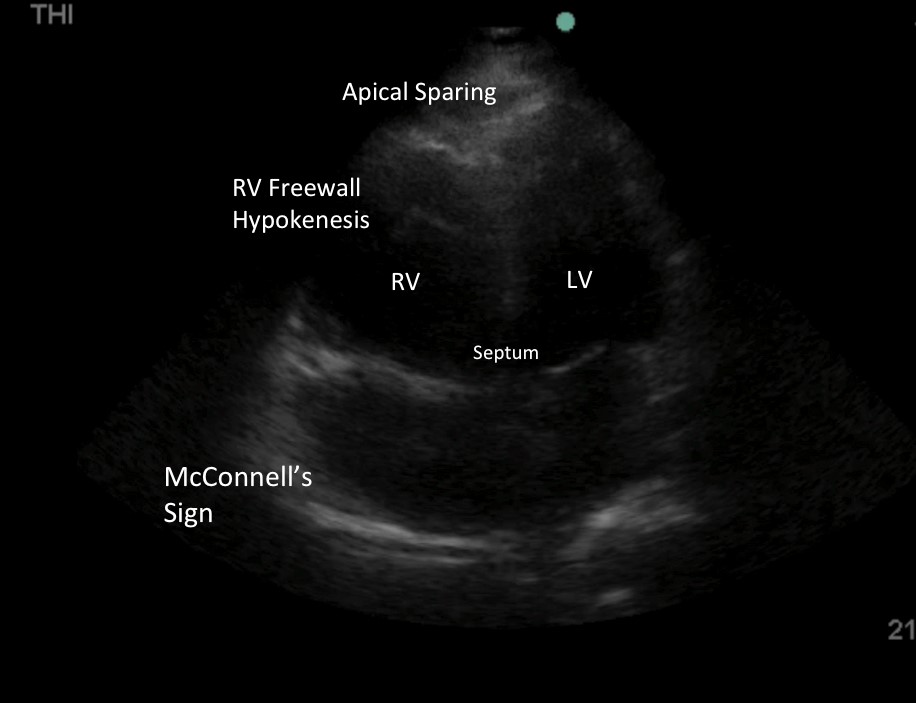

画像5: McConnellのサイン。 RV自由壁の低運動性と先端部の圧迫感が保たれている。 当初のデータでは、McConnell’s signは、慢性の原発性または二次性肺高血圧症(PHTN)で予想されるより均一な運動低下とは対照的に、急性PEの特異的な指標であることが示唆されていました。 最近のデータでは、PHTNでもMcConnell’s signが見られることから、この結論は否定されている8-9。